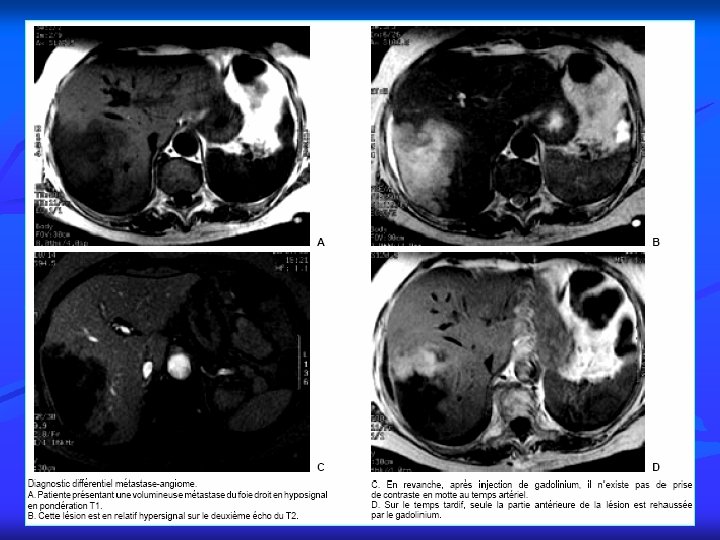

PRINCIPALES INDICATIONS 12 4. Imagerie du foie, des voies biliaires et du pancréas n Pathologie du foie Tumeurs bénignes Tumeurs malignes Cirrhose